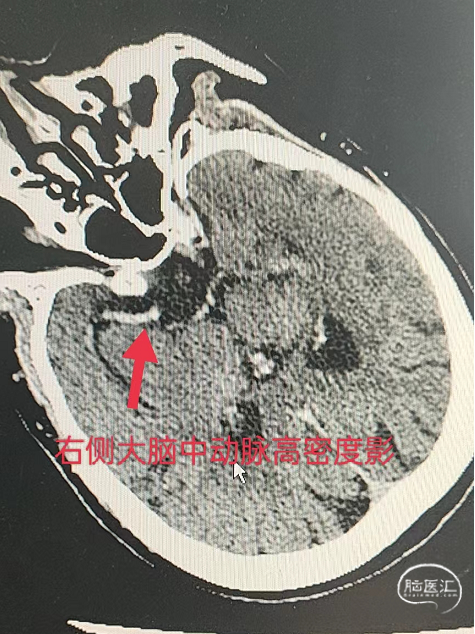

CT示:右侧大脑中动脉高密度影。